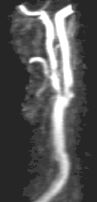

Contrast-Enhanced Subtraction MR Angiography (CE-MRA): State-of-the-art

CE-MRA of the aortic arch and great vessels (left) into the brain, renal arteries (top), selective carotid bifurcation (top right) showing ICA/ECA stenosis, and 3-section run-off (very right) showing multiple stenoses, including long-segment bilateral SFA stenoses.